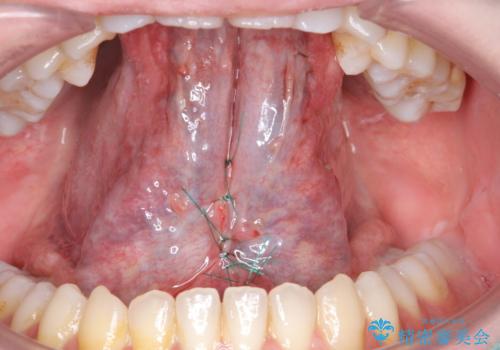

- 滑舌が悪いとの事で来院。

ラ行が言いにくいとの事でしたので舌小帯の形成術を行い、舌の可動域を広げました。

- 舌小帯切除術 3.3万円費用は治療当時の料金となります